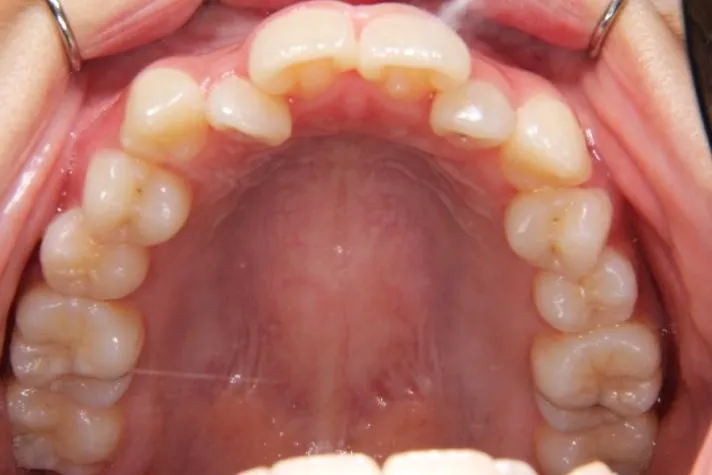

初診時年齢 高校生 (女性) 主訴 歯並びがガタガタ・口元の突出感

診断名 叢生・開咬・上下顎前突 装置名

特徴 ゆがんで生えている

状態 ガタガタ・でこぼこに生えている(叢生)

受け口(下顎前突/反対咬合)

前歯で噛めない(開咬/オープンバイト)

上下前歯、口元が出ている、口ゴボ(上下顎前突)

ガタガタの歯並びにお悩みの患者様でした。

口唇の突出感の他、下顎面高が長い印象も認められました。

歯科矯正アンカースクリューを用いた治療で、非抜歯で口唇突出の改善、臼歯の圧下、叢生の解消を図りました。

叢生は解消し、口元が大幅に引っ込み、下顎面高も縮小しました。